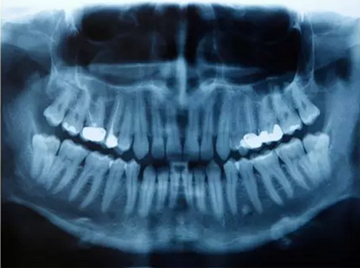

X-线是安全的

当你需要牙科急诊或者某些牙科疾病的诊断时,有时候必须照牙科X-线。牙医或卫生士会给你围上一个围裙,以减少腹部在放射线下的暴露;如有需要,医务人员会在你的脖子上围上一个铅领,以减少甲状腺在辐射下的暴露。